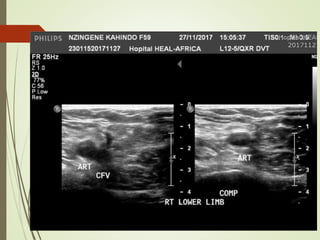

VENOUS

ULTRASONOGRAPHY

 Relies on loss of vein compressibility as the

primary criterion

 About 1/3 of pts will have no imaging

evidence of DVT

 Clot may have already embolized

 Clot present in the pelvic veins (U/S

usually inadequate)

 Workup for PE should continue even if

dopplers (-) in a pt in which you have a

high clinical suspicion